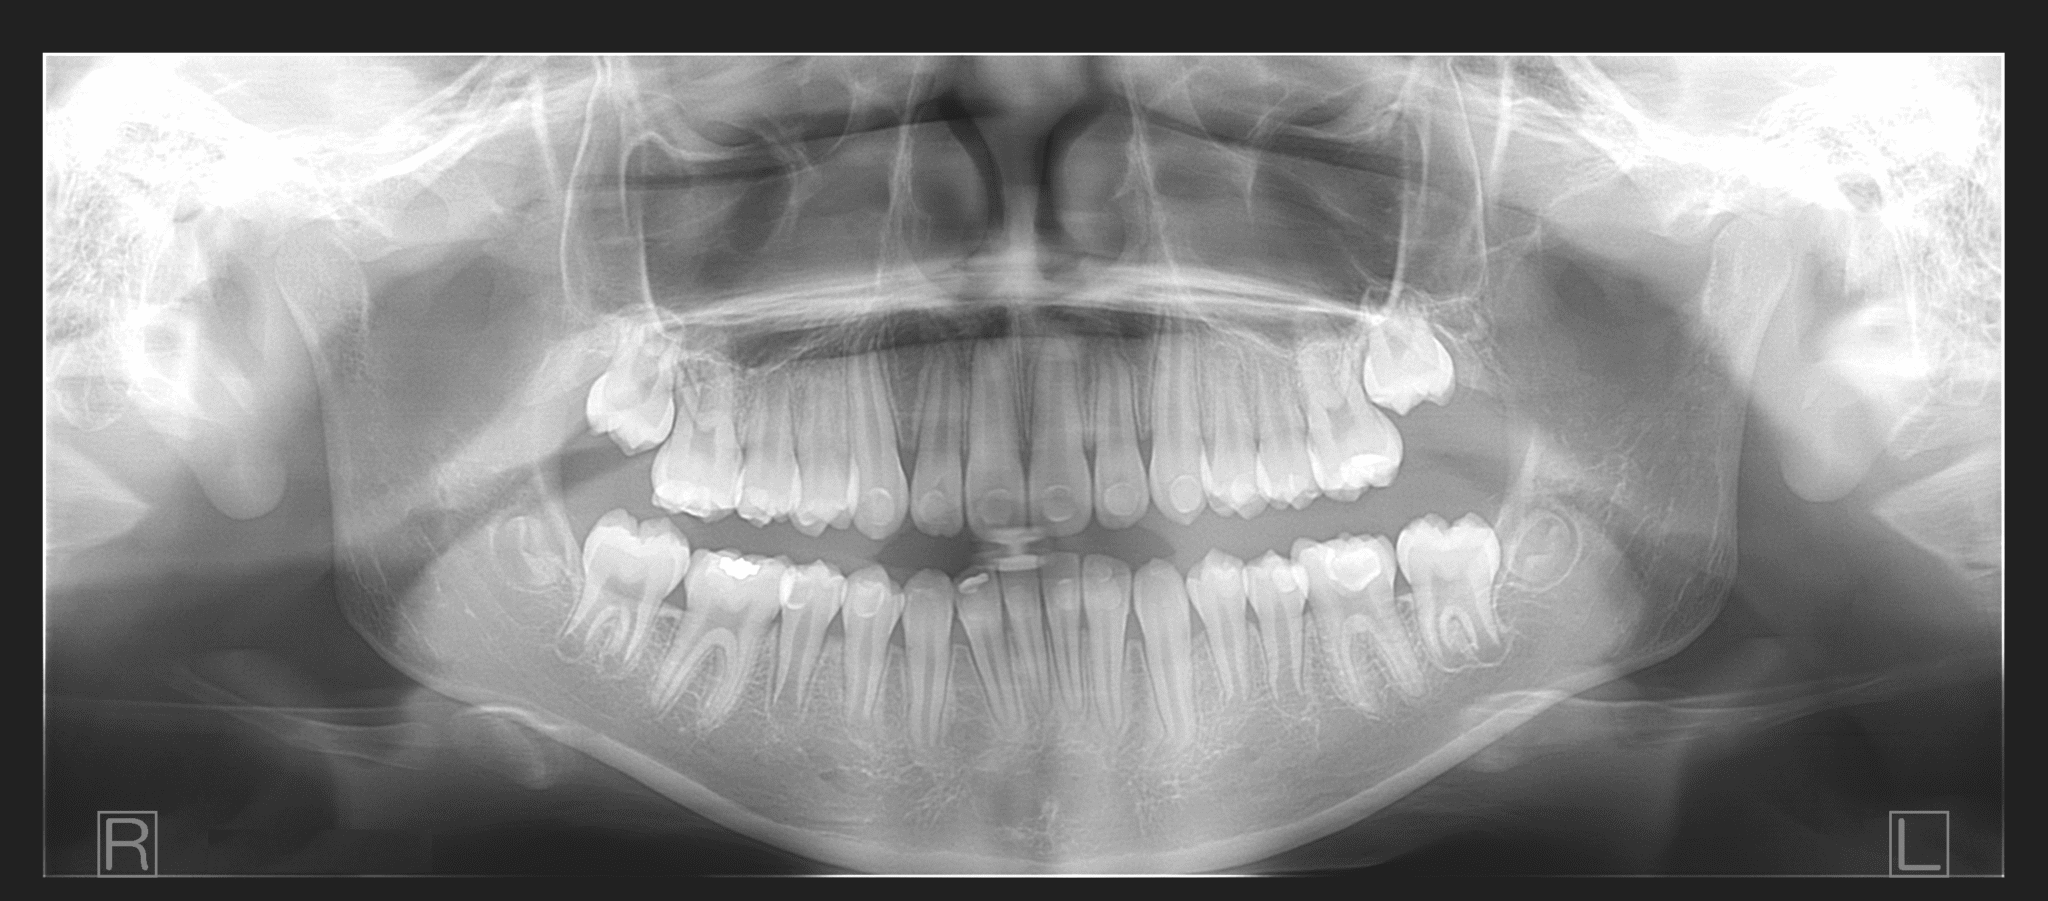

Dental Imaging Ocean Grove . Radius has increased services in the bellarine with a new site opening in ocean grove on monday 4th december. we offer a wide range of diagnostic imaging services as well as musculoskeletal procedures performed under imaging. ocean grove dental clinic has been proudly servicing our beautiful community for over 20 years, providing gentle, personalized and professional dental care. They may be used to assess: Missing, crowded or abnormal teeth. At lake imaging, we offer a number of. 8/10 coastal boulevard, ocean grove vic 3226, australia. radius ocean grove. Lake imaging, make an appointment online or call our dedicated bookings line at our ocean grove location.